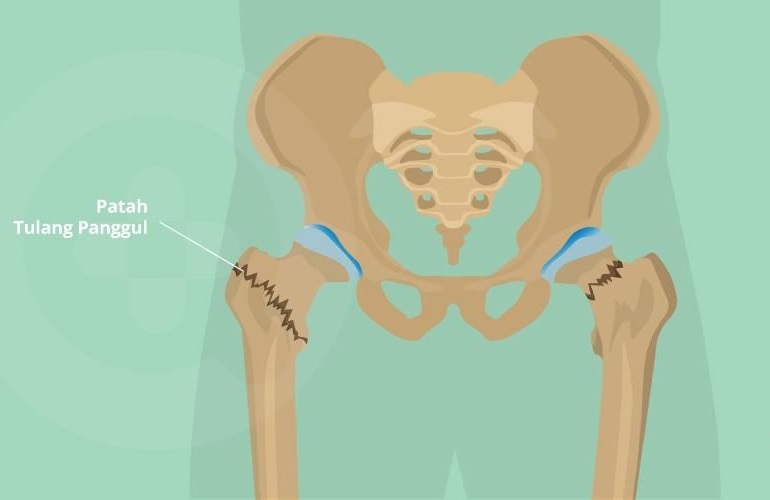

Patah Tulang Pinggul - Gejala, penyebab dan mengobati - Alodokter

Patah Tulang Pinggul - Gejala, penyebab dan mengobati - Alodokter

Patah Tulang dan Resiko Jatuh pada Orang Tua, Apakah Harus Operasi? - Unair News

Patah Tulang dan Resiko Jatuh pada Orang Tua, Apakah Harus Operasi? - Unair News